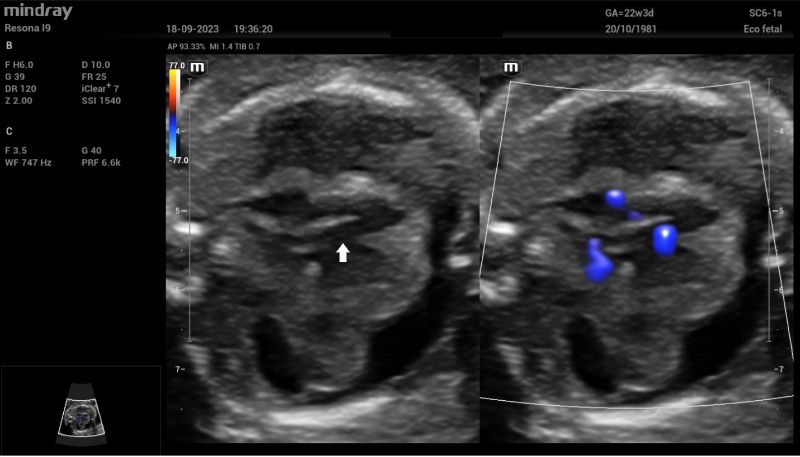

Additionally, a wide muscular ventricular septal defect (VSD) (Fig 2). and agenesis of the ductus venosus with extrahepatic drainage to the inferior vena cava (Fig 3). were diagnosed.

Septal four-chamber view of the fetal heart on dual 2D and Color Doppler imaging. A wide ventricular septal defect (white arrow) is clearly seen

Figure 2: Septal four-chamber view of the fetal heart on dual 2D and Color Doppler imaging. A wide ventricular septal defect (white arrow) is clearly seen.